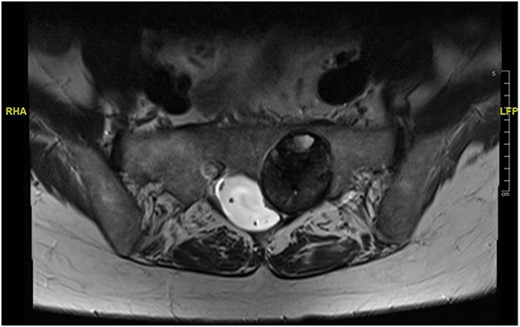

Reviews in July 2019 (with an MRI scan in December 2019) and December 2020 confirmed no neurological deterioration but some increased back and leg pain when standing for some time. A repeat MRI scan confirmed an increase in the size of the lesion (Figs 1 and 2). A biopsy was arranged with a plan for a follow-up surgery. Results of the CT-guided biopsy indicated a diagnosis of metastatic malignant melanoma. Discussions with the patient did not localise any skin lesion responsible for the metastatic deposit, an F18-fluorodeoxyglucose positron emission tomography (18F-FDG PET/CT) scan and a conventional computed axial tomography (CT) scan was organised (April 2021), which revealed sacral destruction and no other deposits in the chest, abdomen and pelvis (Figs 3 and 4). Our patient had a reported SUV of 3.6, indicating a malignant lesion that was then confirmed operatively.